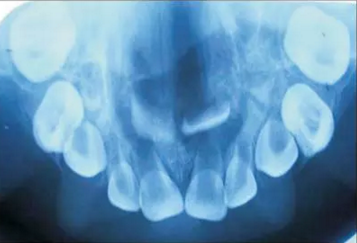

口內(nèi)咬合片可見上頜3×4cm大小低密度影,上頜中切牙恒牙胚移位。

2.png